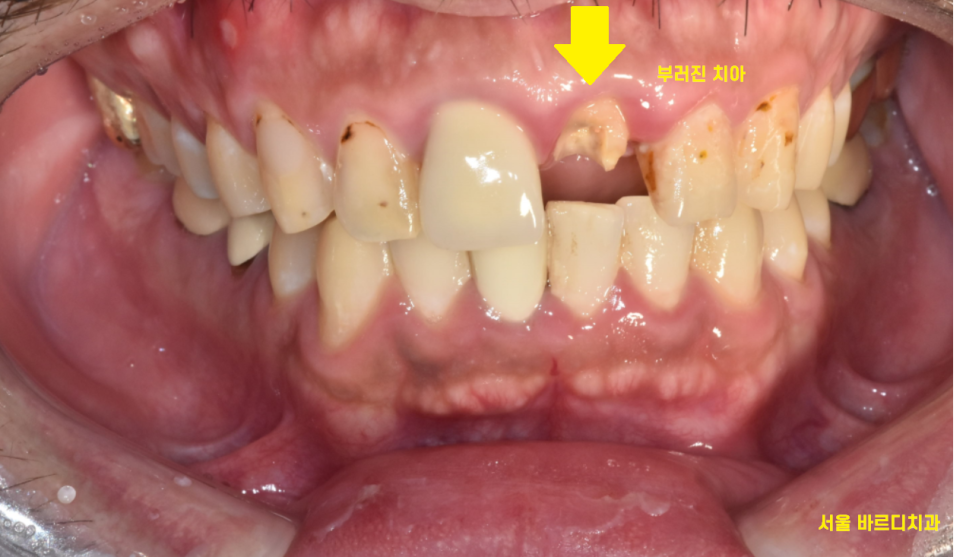

안쪽에서 들여다보니

신경치료때 사용한 재료가 다 보일 정도로

부러졌습니다.

23.12.18